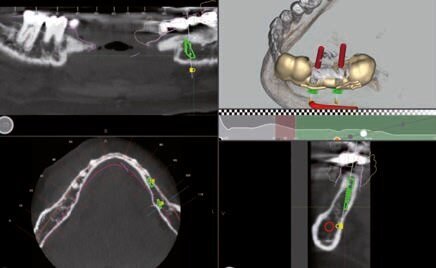

Fig. 4 - Progettazione impianto 35.

Fig. 5 - Progettazione impianto 37.

Fig. 6 - Progettazione dima chirurgica.

Dopo aver valutato con la paziente tutti i pro e i contro abbiamo deciso di prediligere la scelta dei REX PiezoImplant. È stata eseguita un’impronta digitale che è stata accoppiata tramite il software di progettazione all’esame radiografico tridimensionale. Sono stati scelti due impianti REX PiezoImplant 1,8 x 11. L’impronta digitale della situazione pre-intervento della paziente ci ha permesso di utilizzare quest’ultima (come ceratura diagnostica) per programmare il posizionamento implantare in modo protesicamente guidato. La pianificazione software della fase chirurgica e l’utilizzo di una guida per il corretto posizionamento dell’impianto “asse implanto- protesico”, ci hanno permesso non solo di ottenere il posizionamento implantare nel rispetto dello spessore osseo disponibile “asse anatomico” ma anche di ricercare la migliore soluzione protesica avvitata, “asse protesico”, per una sensibile riduzione del rischio di errore. È stata creata una dima chirurgica che ci ha permesso di riportare nel cavo orale la programmazione dell’inserimento implantare che avevamo pianificato virtualmente. La metodica Rex permette di utilizzare una slitta che prevede una chirurgia guidata con sistema Pilot utilizzando l’inserto W2. Sono state raccordate le due preparazioni e le abbiamo estese con l’inserto OT7S3 che ci ha permesso di ottenere una maggiore elasticità ossea.